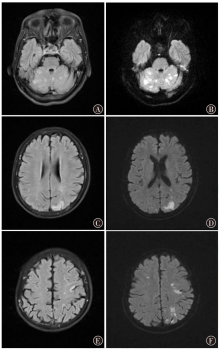

Schwarzbach CJ, Fatar M, Eisele P, et al. DWI lesion patterns in cancer-related stroke—specifying the phenotype[J]. Cerebrovasc Dis Extra, 2015, 5(3): 139-145. DOI: 10.1159/000439549.